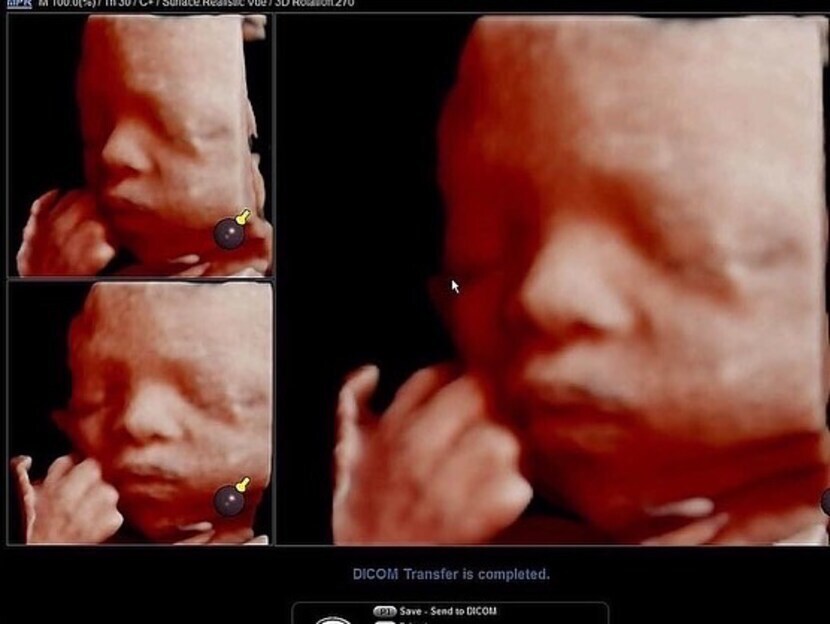

23.03.09 101 읽음 임신중기 4D초음파 스크럼프 구독하기 5 4 콘텐츠의 수익 3 어느덧 중기 후반 이네요 이제 제법 살이 붙어서 더 이뻐졌어요❤️주먹을 꼭 쥐고 잠든것 같죠?ㅋㅋ엄마랑 아빠랑 반반 닮은것 같아요포토샵?처럼 주변에 있는것 지워주시고여러 각도로 인화해 주시네요ㅋㅋ건강하게 만나자❤️ 4 0 / 300 입력